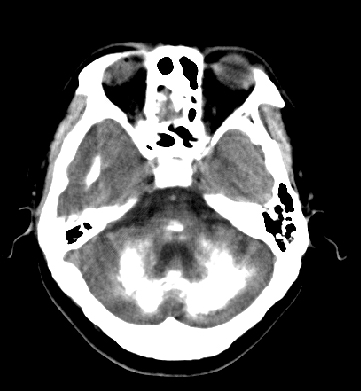

女性 38岁 病人脚弓反张 8岁以后不能行走 今年查pth11.9ng/ml(正常28ng/ml)

谢分享----甲状旁腺功能减退

这么弥漫的钙化还第一次见。

考虑甲状旁腺功能减退症,该病是因甲状旁腺激素分泌减少或功能障碍所引起的少见病。其特点是低血钙,高血磷,且血pth极低。因低钙常可引起神经精神激惹症状,包括手指,趾,口角麻木,严重时可出现肌肉痉挛,喉哮鸣和惊厥,甚至癫痫样发作,有的可出现抑郁症及精神失常。长期的高磷血症可引起脑内结构对称性多发性钙化,特别是小脑和基底节的钙化可致锥体外系症状,而钙化的ct表现为类似于脑出血的密度增高影。

原发性甲状旁腺功能减退症和fahr病都有神志上的改变等症状,且头颅ct检查均可见颅内出现钙化。但fahr病无pth低下,ct表现钙化影在大脑半卵圆中心皮髓质交界处、丘脑、小脑齿状核等处。 而甲状旁腺功能减退症pth极低,ct虽可见钙化影,但部位在小脑和基底节等处。